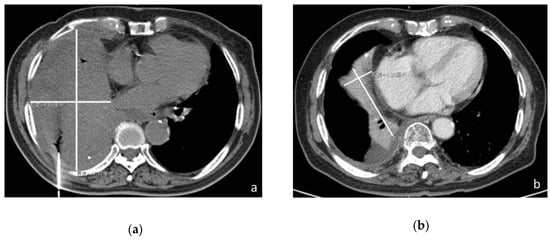

2. Case Report

3.1. Patient Case